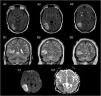

Resonancia magnética cerebral: secuencia FLAIR, cortes axiales (A1-A3), secuencia T2, cortes coronales (B1-B3), secuencias de difusión, cortes axiales (C1=tDWI, C2=ADC). Se observa una lesión córtico-subcortical temporal derecha, hiperintensa en secuencias T2-FLAIR (A y B), afectando a giro temporal medio e inferior derechos, con extensión hacia región peritrigonal y asta occipital del ventrículo lateral ipsilateral. Señal hiperintensa en secuencias de difusión (C1), con restricción de señal en mapa ADC (C2).